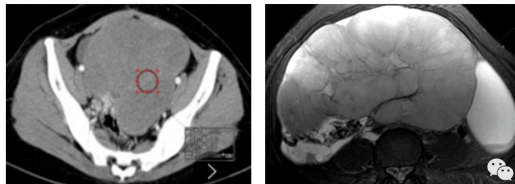

影像表现:子宫右后方见卵圆形软组织肿块影,与子宫后缘密切相连,病灶边缘清晰,病灶呈T1低信号T2低信号为主,其内夹杂少许散在斑片状T2高信号区,增强扫描病灶呈明显强化,与子宫肌层强化类似。盆腔未见明显肿大淋巴结,盆腔见片状压脂明显高信号影。

影像诊断:子宫浆膜下肌瘤。

MRI表现: 是发现和诊断子宫肌瘤最敏感的方法。在T1WI上,子宫肌瘤的信号强度类似子宫肌;然而在T2WI上,典型肌瘤呈明显低信号,边界清楚,与周围子宫肌信号形成鲜明对比。本例病灶与子宫后缘关系密切,病灶边缘清晰,T2呈较低信号,且增强呈明显强化,均符合较典型子宫肌瘤。

不典型肌瘤:退变型:玻璃样变 (>60%),囊变 (~4%),黏液样变,红色样变,水肿不是退变的表现(50%),出血、坏死和钙化 (~4%)。不典型生长部位:腹膜后(阔韧带)、寄生型、宫颈。特殊类型:脂肪平滑肌瘤,黏液性平滑肌瘤,浆膜下子宫肌瘤。